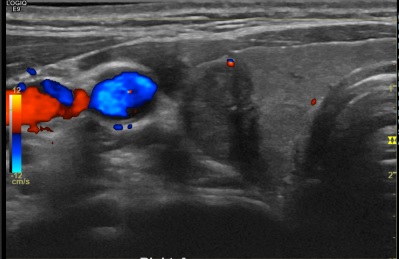

상기환자  외부 건진상 이상소견으로 내원하신 40대후반 여성분으로 의심스러운 갑상선 우엽 결절 세포검사진행, 반절제 시행후 갑상선암으로 진단되었습니다